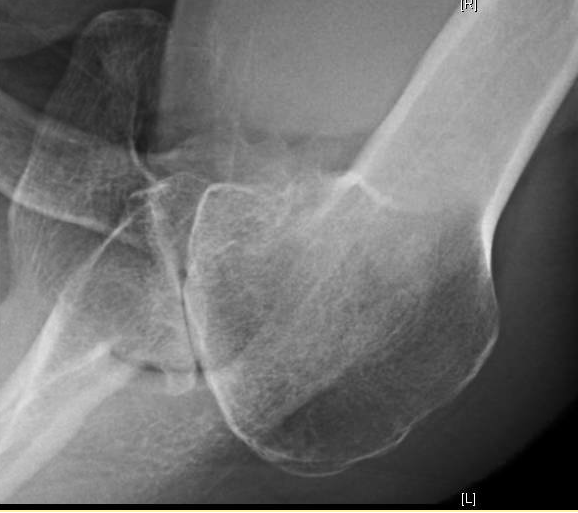

Shoulder Arthritis / Joint Replacement Evaluating the arthritic Shoulder Pain Arthritis Or Rotator Cuff Injuries to the rotator cuff are common and can lead to a form of shoulder arthritis called rotator cuff tear arthropathy. Rotator cuff tear arthropathy is a type of shoulder arthritis that can develop after a massive and prolonged rotator cuff tear. In the shoulder, arthritis causes pain and stiffness that can make it difficult to lift your arm, brush. Shoulder Pain Arthritis Or Rotator Cuff.